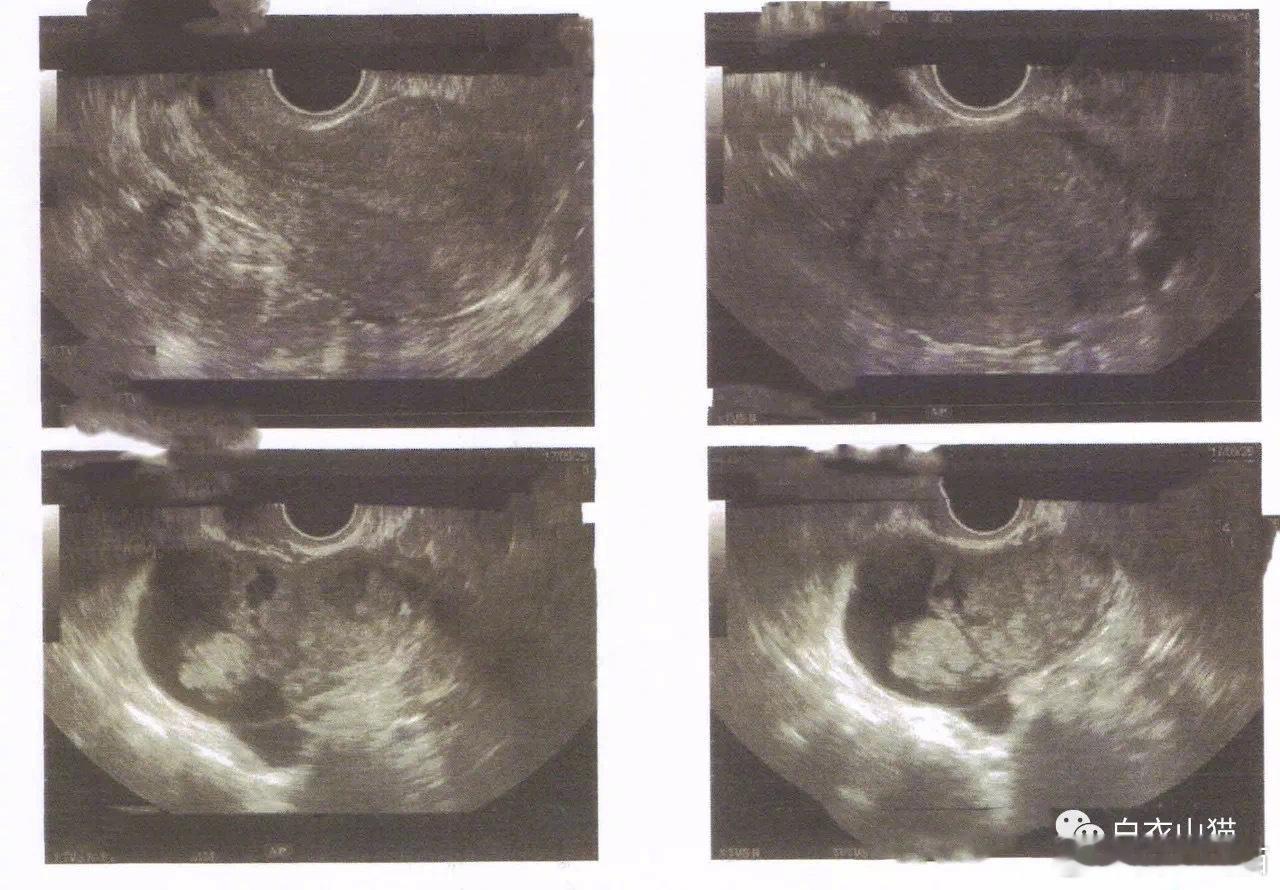

图片3

她的B超结果,右侧卵巢有个直径8厘米的肿块

做完检查,有了结果。她的妇科B超上,显示出她的右侧卵巢有个直径8厘米的肿块。

她的血液化验结果:CA125:260.5 IU/ML,(正常是0到35 IU/ML)CA199:192.3U/ML (正常是0到35 U/ML)。结合妇科B超和血液CA125和CA199,医生已经高度怀疑她患了右侧卵巢癌了。